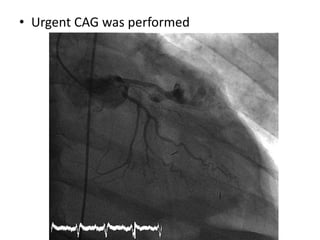

• Urgent CAG was performed

• CAG- Extravasation of contrast from LAD –

perforation at the site of previous stent

placement.

• Pt was taken up for surgical correction of LAD